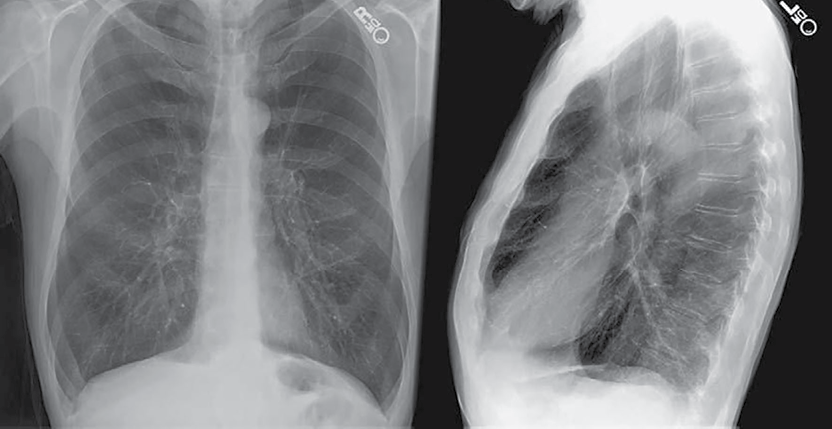

Para el diagnóstico de la EPOC es importante conocer los antecedentes de exposición a factores de riesgo, y la presencia de los principales síntomas (disnea, tos, producción de esputo, opresión torácica, sibilancias y congestión del pecho); es esencial una historia clínica bien detallada donde se recabe la mayor cantidad de datos de todo nuevo paciente en el que se conozca o se sospeche de EPOC, y una espirometría para establecer el diagnóstico (figura 3).

Foto: Martínez et al.

Figura 3 Enfisema: radiografía de tórax, en dirección postero-anterior y lateral, donde se muestra hiperinflación pulmonar (diafragmas aplanados y espacio retroesternal amplio), así como aumento de la radiolucidez en los ápices pulmonares con atenuación de los trayectos vasculares con arborización distorsionada.